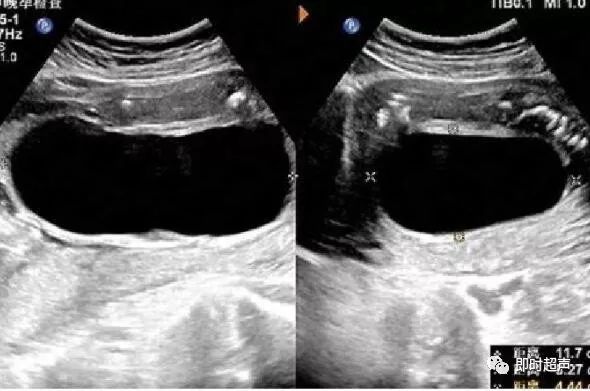

【请教】wes征——w回声 - 超声医学讨论版 -丁香园论坛

唐氏综合征——大排畸时也要警惕_超声